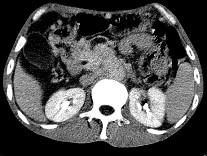

问题 女,50岁,中上腹疼痛,消瘦乏力,影像检查如下图,最佳的诊断是()

选项 A.慢性胰腺炎 B.急性胰腺炎 C.胰腺癌并腹膜后淋巴结转移 D.胰岛素瘤 E.腹膜后淋巴瘤

答案 C